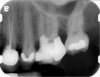

Clinical procedure: If apical bone loss is present (Figure 1) a collagen/gelatin sponge (eg, Gelfoam®, Pfizer Inc., www.pfizer.com) can be placed apically so that the MTA can be delivered to the desired working length. (Any other surgical resorbable sponge would also work, such as OraPlug® [Salvin Dental Specialties, www.salvin.com], Surgifoam® [Midwest Dental, www.mwdental.com], or Surgispon® [Aegis Lifesciences, www.surgispon.com]). This is done by taking a small piece (2 mm x 2 mm) of the resorbable sponge and pushing it down to and through the root apex with an endodontic file. Once this is done, MTA is packed down the canal with a custom-fitted cone. The clinician can use a rubber stopper on the gutta-percha cone to know the exact length of MTA placed in the apical third (Figure 2). Once the apical third is sealed with 3 mm to 5 mm of MTA, the remaining coronal canal space can be back-filled using a warm gutta-percha technique (Figure 3).

Fig 2. MTA placed in the apical third.

Figure 2

Fig 3. Postoperative radiograph.

Figure 3